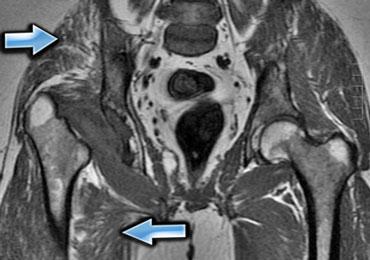

Hình bên trái là một ví dụ, lưu ý các thay đổi viêm ở các cơ lớn vùng mông.

Sau khi ngừng thuốc, đau cơ sẽ biến mất trong khoảng 2 tuần, tuy nhiên MRI vẫn còn cho thấy bất thường cho đến khoảng một tháng sau đó.

Thời điểm tốt nhất để chụp MRI theo dõi là khoảng 6 tuần sau khi ngừng thuốc.

Đây là bệnh nhân cao tuổi có tăng cholesterol máu được chỉ định dùng Lipitor.

Bệnh nhân xuất hiện đau nhức cơ, CPK tăng nhẹ.

Các thay đổi khá tinh tế, chúng ta thấy các ổ tụ dịch quanh mạc cơ, ở rìa ngoài của cơ (ngoại mạc cơ).

Ngoài ra còn có thay đổi da tối thiểu.